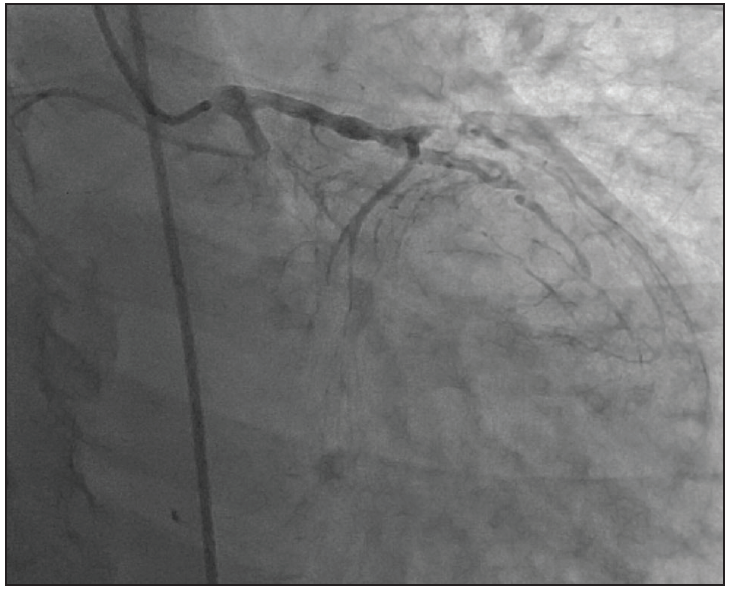

A 71-year-old active man with no regular medical follow-up presented with stuttering chest pain of 2 days’ duration and was found to have an inferior ST-segment elevation myocardial infarction (STEMI). His initial troponin I level was 39.5 ng/mL, and he was urgently taken for cardiac catheterization, which demonstrated a nondominant right coronary artery, totally occluded large mid–left circumflex artery, and chronic total occlusion (CTO) of the mid–left anterior descending (LAD) artery (Figure 1). Hemodynamic assessment performed at the time was consistent with cardiogenic shock (right atrium [RA], 12 mm Hg; pulmonary artery [PA], 46/25, 32 mm Hg; pulmonary capillary wedge pressure [PCWP], 24 mm Hg; cardiac index, 1.7 L/min/m2).